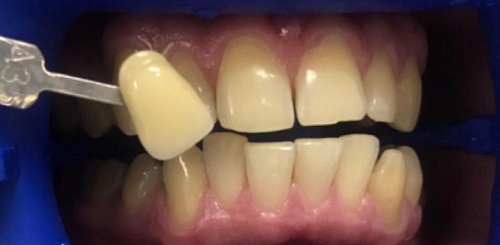

Изменения тканей, которые окружают корни зубов, к сожалению, неизбежны и с возрастом наблюдаются у всех, однако в разном объеме. Так, на развитие пародонтита влияет болезнетворная микрофлора полости рта, которая есть у каждого из нас, но на мы в силах повлиять на ее количество.

Сохранить зубы и пародонт помогает правильная гигиена полости рта дома и в кресле стоматолога, а также своевременное протезирование и имплантация, которые замещают удаленные зубы и равномерно распределяют жевательную нагрузку, не позволяя костной ткани атрофироваться.

Таким образом, по мнению стоматологов, риск возникновения болезней десен на 80% зависит от сознательности самого пациента.